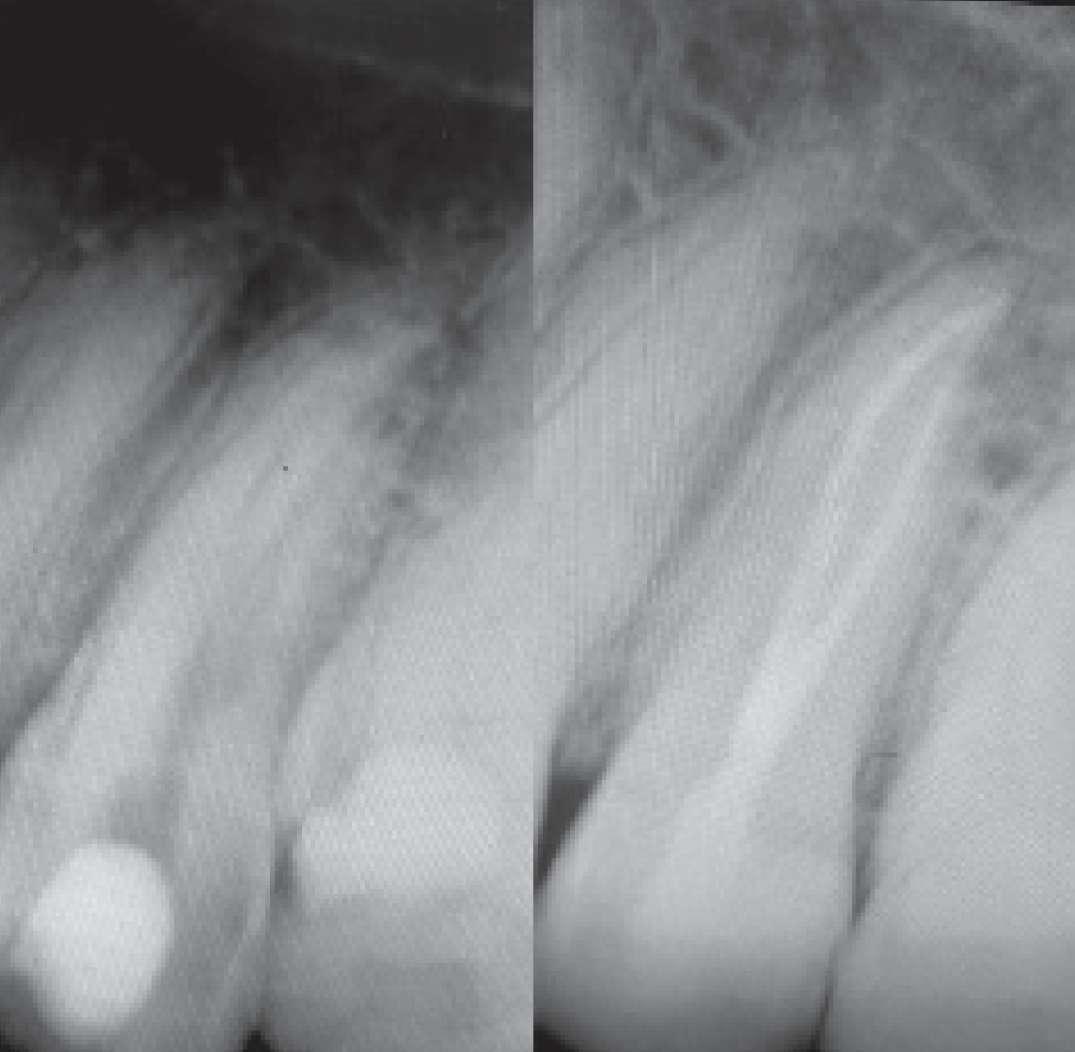

Dank der Flexibilität und Benutzerfreundlichkeit der EdgeOne-Fire-Feilen konnte ich diesen. Wurzelkanal schnell und sicher abschließen. Prä- und postoperative Bilder, die im Abstand von 4 Monaten aufgenommen wurden, zeigen Anzeichen einer erfolgreichen Heilung und kein Vorliegen einer Fistel. Ich denke, diese Feilen sind großartige Werkzeuge, die jeder Kliniker haben sollte.

Präop. vs. postop.

Röntgenaufnahmen im Abstand von 4 Monaten

DIVERGIERENDE KANÄLE

Divergierende Kanäle (zwei Kanäle, die zusammen beginnen und sich dann im mittleren / apikalen Teil der Wurzel trennen) stellen ein klinisches Problem in der Endodontie dar, insbesondere bei der Verwendung traditioneller NiTiInstrumente. Aufgrund des superelastischen Verhaltens der Legierung können die Instrumente dem gleichen Kanal folgen (und zwar dem, der gerader ist) aber es ist schwieriger, den zweiten zu finden, insbesondere dann, wenn man den Eingang unmöglich wegen seiner Tiefe in der Wurzel sehen kann.

ZIEL

Der vorliegende Fall zeigt den klinischen Vorteil der Verwendung einer Einzelfeil-Reziprokationstechnik mit einer wärmebehandelten vorgebogenen martensitischen Feile (Edge One Fire) bei der Behandlung divergierender Kanäle auf.

FALLGESCHICHTE

Untere Prämolaren können manchmal zwei oder drei Kanäle aufweisen. Eine solche ungewöhnliche Anatomie ist oft mit engen, stark gekrümmten, konfluenten oder divergierenden Kanälen verbunden. Der letzte Fall ist sehr komplex und erfordert in der Regel den Einsatz von Instrumenten, welche in zwei verschiedenen Kanälen ( daher flexibel und präbendal ) mit unterschiedlichen Winkelstellungen ausgerichtet werden können. Ein angemessener Gleitpfad hilft auch bei der NiTi-Formung, er löst aber nicht immer das Problem. Daher wurde im vorliegenden Fall die primäre EinzelfeileReziproziertechnik EOF verwendet. Die Instrumente wurden in ihrem apikalen Teil vorgeformt, in die beiden verschiedenen Kanäle eingeführt und dann aktiviert. Die Wahl der Instrumente war effektiv, weil die mechanischen Eigenschaften des EOF-Primärs (flexibel und vorgebogen) es ermöglichen, präzise und einfach in jeden Kanal eingeführt zu werden und diese dann zu behandeln. Die Verwendung einer einzigen Feiltechnik ermöglichte es, sich der Herausforderung eines divergierenden Kanals nur einmal zu stellen, was Zeit spart und die Komplexität reduziert. Die Verwendung traditioneller Instrumente kann in vielen Fällen helfen, den Weg mit kleineren und flexibleren Instrumenten zu finden, aber nicht mit größeren. Durch die Verwendung von nur einer Feile erwies sich das gesamte Verfahren als einfacher und schneller, sodass beide Kanäle korrekt geformt, gereinigt und abgedichtet werden konnten.

Eine Single-File-Reziprozierungstechnik mit einer wärmebehandelten vorgebogenen martensitischen Feile (Edge One Fire) erwies sich als ausgezeichnete, einfache und schnelle Option für die Instrumentierung von divergierenden Kanälen.